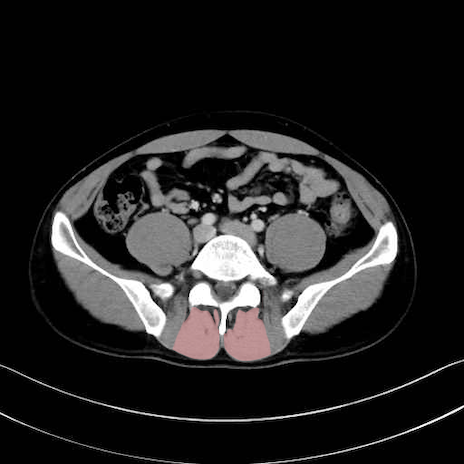

肛門挙筋 (Levator ani)